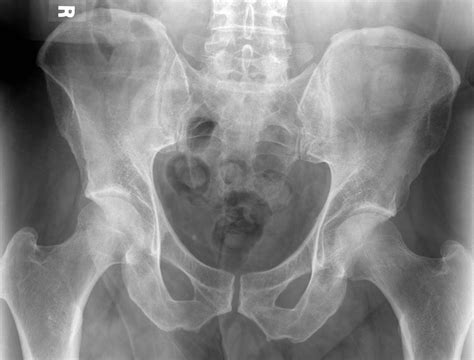

Many men often overlook the health and well-being of their lower body until a specific issue arises. However, taking proactive steps to understand and care for the men's pelvic area is essential for long-term health, comfort, and vitality. This complex region, which encompasses the muscles, nerves, and organs situated in the lower part of the torso, plays a pivotal role in daily bodily functions, including bladder control, bowel health, and sexual function. Neglecting this area can lead to chronic discomfort or dysfunction, yet it remains a topic that many men feel hesitant to discuss or actively maintain.

The men's pelvic area is supported by a sophisticated network of muscles, collectively known as the pelvic floor. These muscles act like a hammock, supporting the bladder, bowel, and prostate. When functioning correctly, they allow for voluntary control over these organs. However, when these muscles become too weak or, conversely, too tight (hypertonic), it can lead to a variety of issues.

A specialist can conduct a thorough evaluation, which may include physical examinations, imaging, or specialized physical therapy techniques to help diagnose and treat the specific issue affecting the men's pelvic area.

- picture of male pelvic area

- diagram of male pelvis